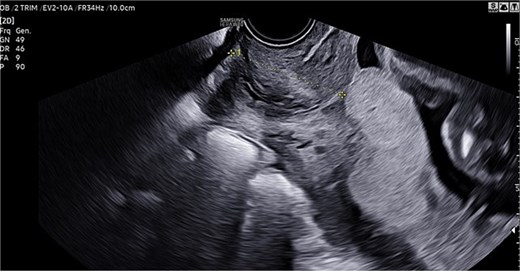

The suture technique involved passing the needle through the uterine cavity from anterior to posterior, exiting the posterior wall, and reinserting it 2–3 cm laterally from posterior to anterior. The needle was then passed again from anterior to posterior, exiting the posterior wall ~2–3 cm below the previous exit site. Finally, the stitch was completed by reinserting 2–3 cm laterally into the posterior wall. The two ends of the thread were tied using a flat surgical knot to enhance compression. Both sutures were placed medially along the posterior wall at the level of the cervical isthmus (Fig. 2).

Hemostatic suture with modified Cho stitches on the posterior wall and cervical isthmus.